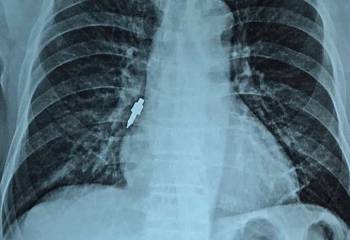

Bác sĩ Võ Thành Nam, Phó Trưởng Khoa Thận – Lọc máu, Bệnh viện Quân y 175 cho biết, ngày 14/7, đơn vị tiếp nhận 3 trường hợp gồm: chị N.T.T.A (37 tuổi), em N.X.H (16 tuổi) và anh T.K.H (41 tuổi), đều ngụ tại tỉnh Bình Phước. Cả 3 trường hợp được chuyển đến trong tình trạng lơ mơ, suy hô hấp. Qua khai thác bệnh sử kết hợp với các xét nghiệm cận lâm sàng, các bác sĩ nhận định 3 nạn nhân bị ngộ độc methanol nặng. Sau khi chuyển đến Bệnh viện Quân y 175, cả 3 nạn nhân đều được tiến hành lọc máu cấp cứu với chẩn đoán ngộ độc methanol giờ thứ 44, tiên lượng nặng. Hai giờ sau lọc máu, các triệu chứng bắt đầu cải thiện. Đến sáng 15/7, ba nạn nhân bước đầu đáp ứng tốt với lọc máu. Trong đó, em N.X.H (16 tuổi) hồi phục hoàn toàn, hai người còn lại đã tỉnh táo.